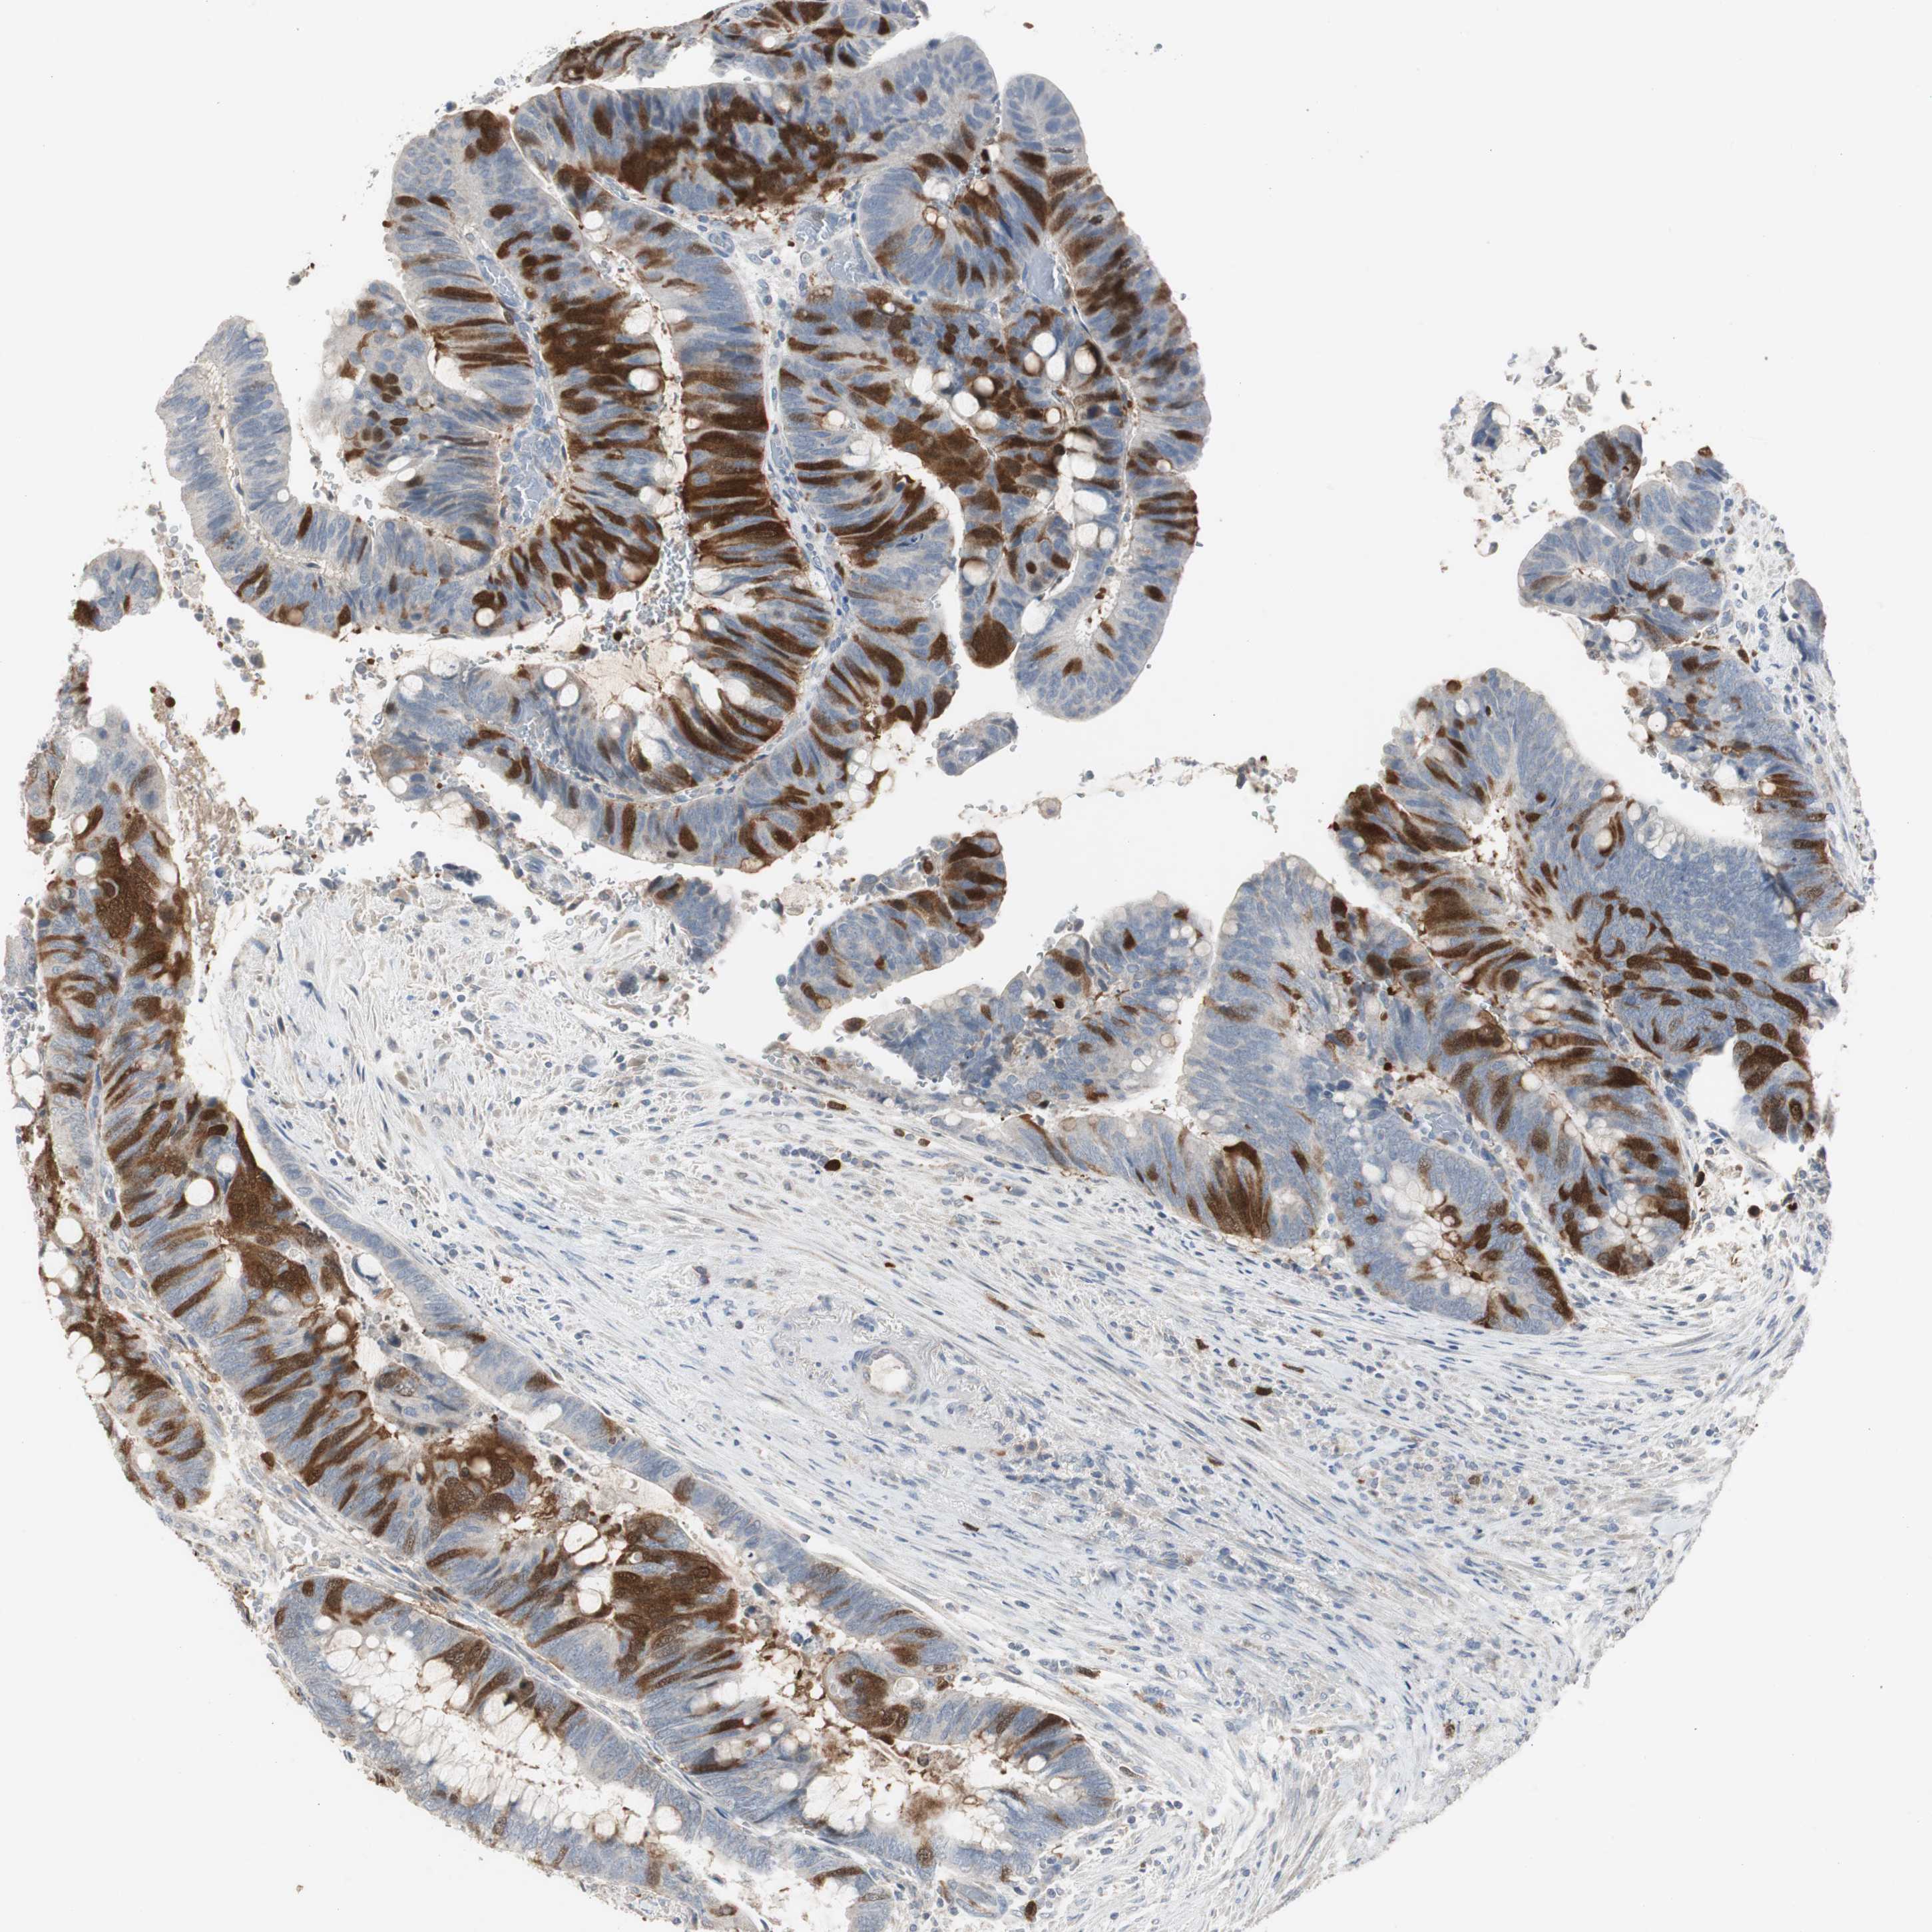

ANTIBODIES

AND

VALIDATION